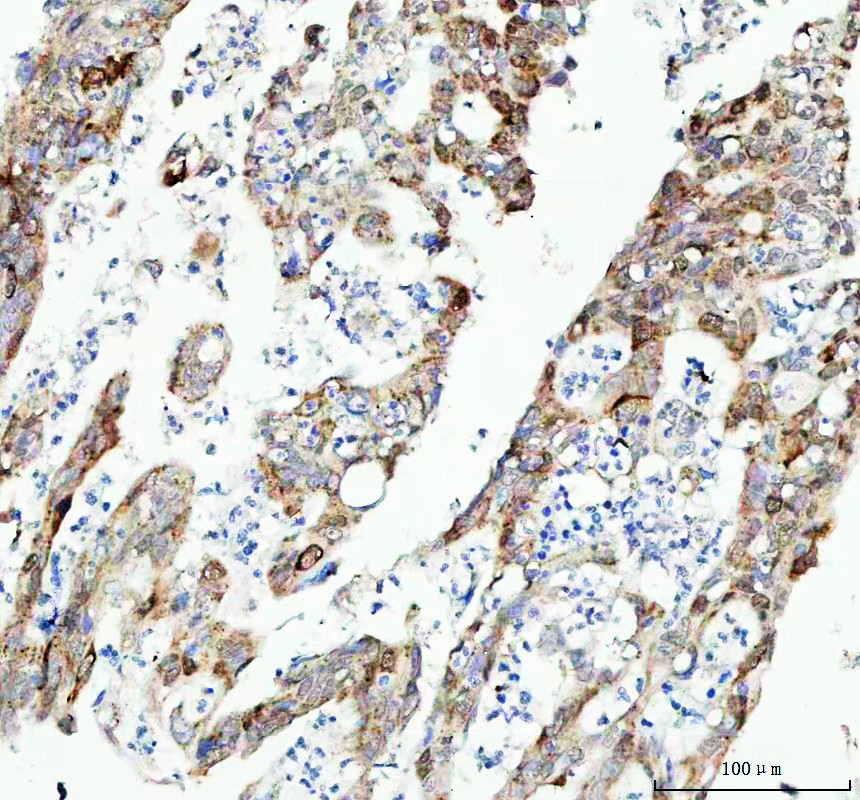

IHC analysis of CDK1 using anti-CDK1 antibody (BM4062) .

CDK1 was detected in a paraffin-embedded section of human lung adenocarcinoma tissue. The tissue section was incubated with rabbit anti-CDK1 Antibody (BM4062) at a dilution of 1:200 and developed using HRP Conjugated Rabbit IgG Super Vision Assay Kit (Catalog # SV0002) with DAB (Catalog # AR1027) as the chromogen.